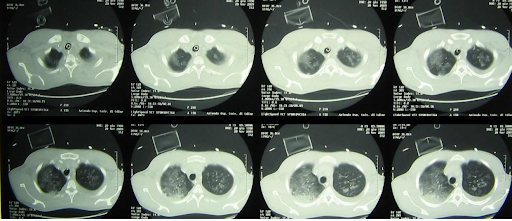

Die Bildgebung des Brustkorbs zeigt nun eine fast vollständige beidseitige Trübung der Lunge. Die Echokardiographie zeigt eine globale Hypokinesie, die im rechten Ventrikel stärker ausgeprägt ist, ohne Anzeichen einer Endokarditis.

ARDS_2.png

Brust-CT während des Aufenthalts auf der Intensivstation zeigt diffuse beidseitige milchglasartige Trübungen und Verdichtungen, die mit schwerem ARDS vereinbar sind.1